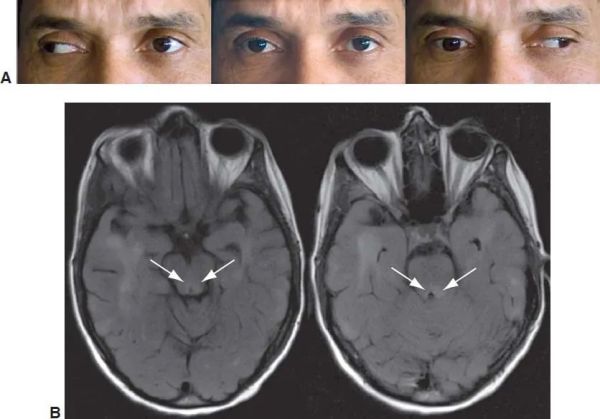

A good ocular examination is often all that is required to diagnose INO. The INO is characterized clinically by an ipsilesional adduction deficit (partial or complete) with a contralateral, dissociated, horizontal abducting saccade or nystagmus on attempted gaze to the contralesional side. There is a slow adducting saccadic velocity in the affected side. A skew deviation with the ipsilateral hypertropic eye may be noted. Vertical gaze nystagmus may be noted on upgaze. The INO can be unilateral or bilateral and may present with or without (neurologically isolated) other brainstem findings.

Imaging tests, such as a CT (computed tomography) scan or MRI (magnetic resonance imaging) brain (stroke protocol and with contrast for demyelination), are ordered after a diagnosis is made to discover where the damage is located so that the physician can then assess which approach to take. In general, MRI is superior to CT scan for evaluation of INO. MRI should involve fine overlapping cuts to ensure detection of lesions that may be very small and may otherwise be missed. Proton density imaging was noted to be the preferred modality to identify MLF lesion in multiple sclerosis with INO when compared to T2-weighted imaging, and fluid-attenuated inversion recovery (FLAIR) imaging.[39] Diffusion-weighted imaging with MRI may detect brainstem infarcts causing INO that may not be detected with T2-weighted imaging alone.[24]